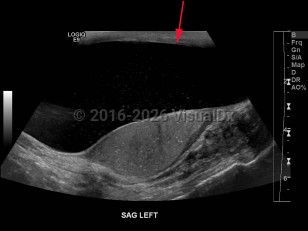

A hydrocele is an accumulation of serous fluid between the visceral and parietal layers of the tunica vaginalis, which covers the testes and spermatic cord. Hydroceles may be communicating or noncommunicating. A communicating hydrocele results from failure of closure of the tunica vaginalis leaving a patent process. This is most common in newborns. The fluid is often reducible. Noncommunicating hydroceles have no connection to the peritoneal cavity and are not reducible.

A hydrocele often presents as a painless visible or palpable cystic mass in the scrotum and otherwise is usually asymptomatic.

Typically, a male newborn patient presents with painless scrotal swelling on one or occasionally both sides. Usually, the hydrocele will go away on its own within the first year of life without medical intervention. An adult man who presents with a hydrocele may experience discomfort, a feeling of heaviness or fullness, or induration and irritation of the scrotal skin.